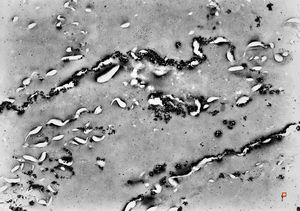

F, 39y. | collagenous and elastin fibers from corium

F, 39y. | collagenous and elastin fibers from corium

F,68y. | collagenous and elastin fibers from corium